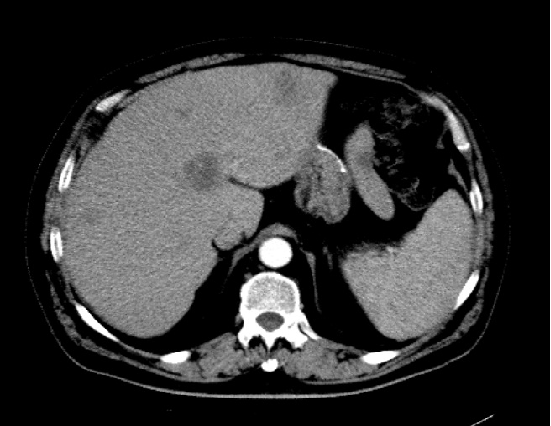

2018-06:肝脏局部灌注异常,实质内多发小斑片状影。

2018年06月:肝脏局部灌注异常,实质内多发小斑片状影

影像学复查:(贝伐+ 伊立替康+雷替曲塞方案)

2018年09月平扫:未见特殊异常

胸腹盆增强CT(2020-05-08):直肠癌治疗术后,左下腹造瘘术后,肝脏多发转移较前增多增大,双肺气肿,主动脉及冠状动脉硬化,双肾囊肿